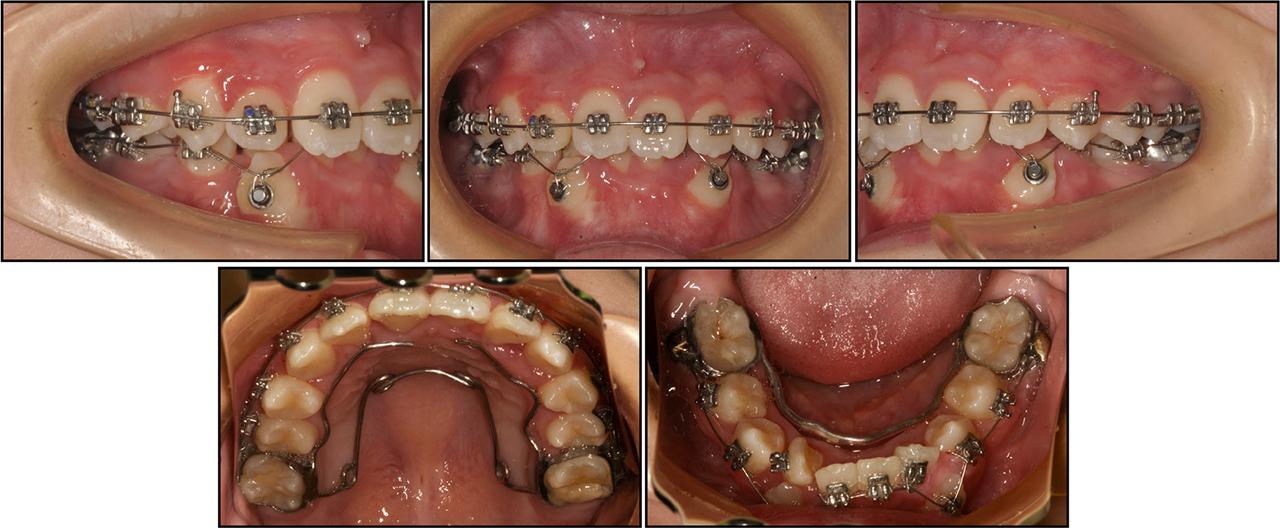

Figure 3